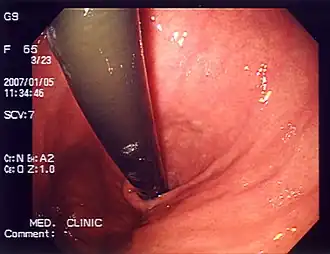

Endoscopy photo of a peptic ulcer

Peptic ulcer, a differential diagnosis for heartburn,[8] in the gastric antrum

The differential diagnosis, a process used by healthcare professionals to help differentiate a diagnosis from other similar disorders,[9] for heartburn includes motility disorders such as achalasia and gastroparesis; peptic ulcers; functional dyspepsia; angina;[8] eosinophilic esophagitis; coronary artery disease; functional heartburn;[10] peristalsis; acid reflux; inflammation of the esophagus (esophagitis), stomach (gastritis), pancreas (pancreatitis), gallbladder (cholecystitis), and duodenum (duodenitis); esophageal cancer; ischemic pain; hiatal hernia; biliary colic; stomach cancer; gallstones; pancreatic cancer; duodenal ulcer; and mesenteric adenitis.[4] Heartburn can also be caused by certain medications such as nonsteroidal anti‐inflammatory drugs, corticosteroids, tetracycline antibiotics, bisphosphonates, calcium‐channel blockers, nitrates, tricyclic antidepressants, and anticholinergics.[4]